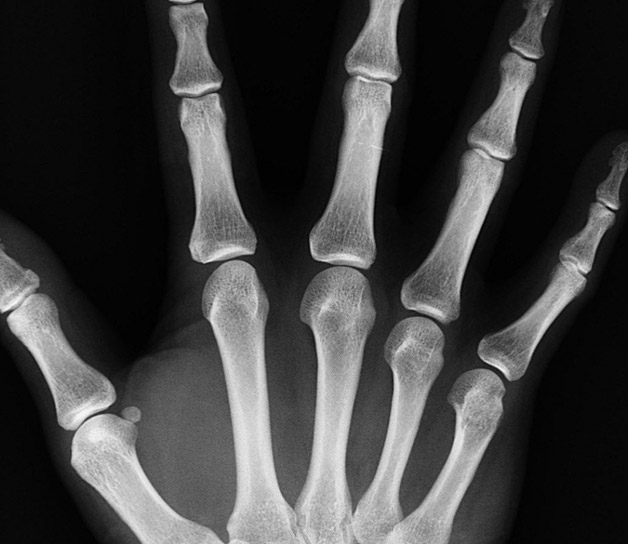

CARPO

Estudio específico para determinar la edad ósea

Durante el tratamiento ortodóncico de las maloclusiones es fundamental la evaluación del crecimiento óseo del paciente dado que la mayoría está en edad de desarrollo.

La edad cronológica no siempre coincide con la madurez ósea, por lo que en ocasiones el ortodoncista solicita un estudio específico para analizar en que etapa se encuentran los huesos del paciente y conseguir que el tratamiento de ortodoncia modifique el crecimiento en función de ello.

El método más extendido para determinar la edad ósea de un paciente es a través de una radiografía de la mano izquierda, incluyendo la muñeca. Los parámetros que ofrece son considerados universalmente como un auténtico reloj biológico.

En nuestro Clínica Dental en Carabanchel contamos con la última tecnología digital en Radiología Dental de última generación, lo que nos permite obtener imágenes sumamente precisas con la menor radiación para el paciente.